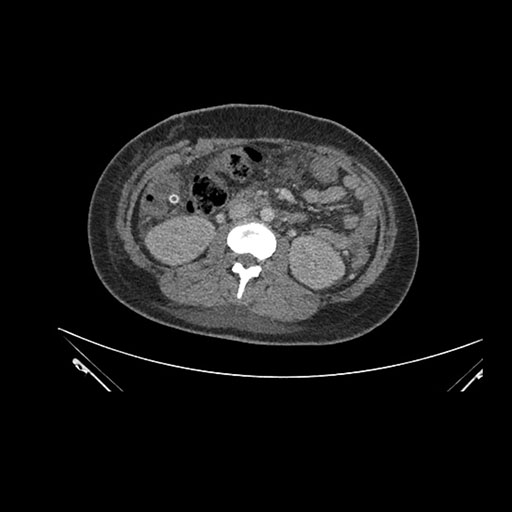

Axial Venous